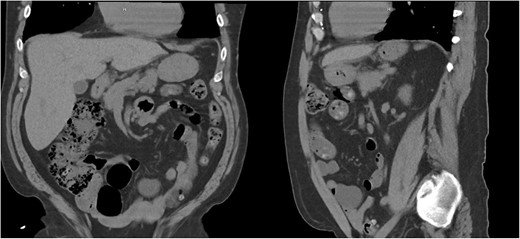

He underwent a CT scan ten months after surgery for flank pain with suspected nephrolithiasis, which demonstrated the successful repair (Fig. 6).